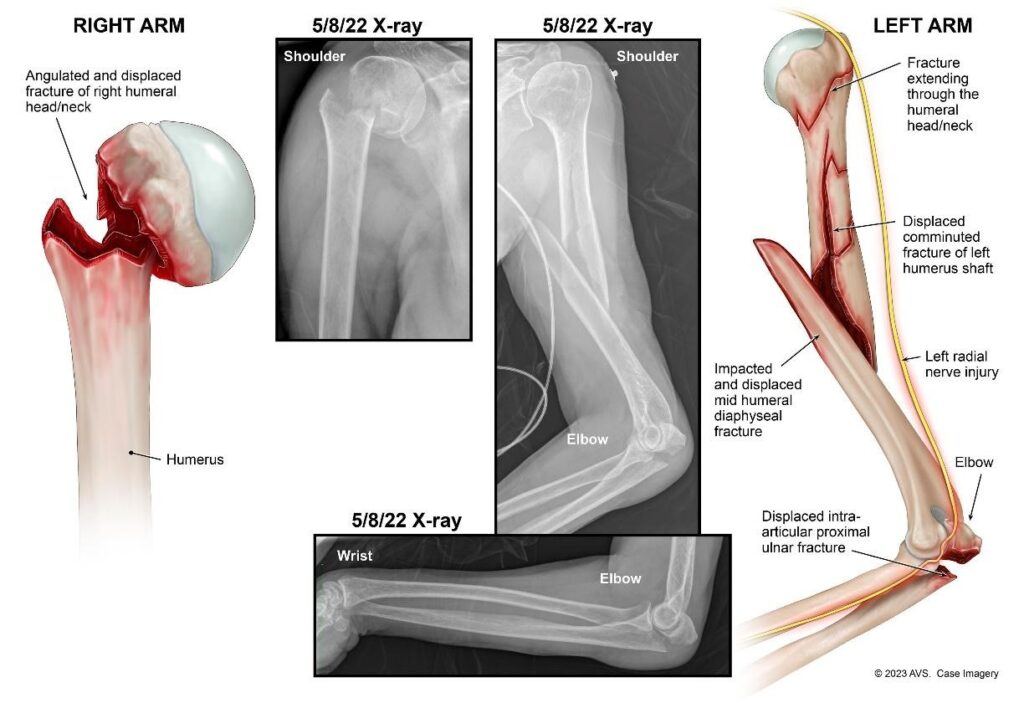

The force of the impact caused multiple fractures to both of our client’s arms, a nasal bone fracture and traumatic brain injury, a facial laceration requiring stitches, extensive bruising across her body, and fractures to her cervical spine, left foot, and right pinky finger. Our client was hospitalized for several weeks while she underwent multiple orthopedic surgeries to repair the fractures to both of her arms, followed by a long and painful period of rehabilitation.

Medical illustrations show the severity of our client’s fractures in her arms

Our client’s left arm was so badly broken that doctors had to drill a metal rod through the humerus (upper arm), wrap wires around the multiple pieces of broken bone, and screw metal plates into our client’s elbow. The radial nerve, which runs alongside the humerus and down the arm, was also injured. This caused our client to suffer from “wrist drop,” meaning that our client was unable to lift her left hand. In order to show the jury what this surgery involved, Butler Kahn obtained medical illustrations detailing the procedure step-by-step (link to one, link to two), and worked with our client’s surgeon to make sure the illustrations were accurate.